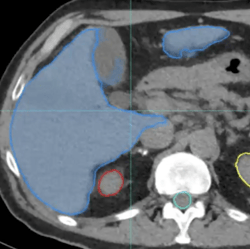

Lung: 2D Fill Tool + Contour CoPilot

With Contour ProtégéAI+, a majority of the slices in the lung contour are accurate without manual work, saving significant contouring time. In this example, however, a few slices at the bottom of the lung — represented here with the yellow contour — need to be adjusted.

2d fill tool

The 2D Fill tool is used to correct the contour on one slice due to a steep drop-off in Hounsfield units. With Contour CoPilot, the corrected contour can be instantly deformed to the next slice with one click.

To complete the process, Contour CoPilot is used to correct any remaining adjacent contours.